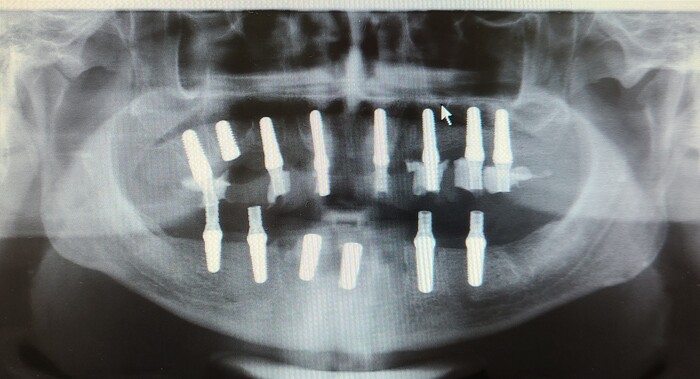

Имплантация обеих челюстей. Что было, что есть и что будет (мой личный случай из жизни)

Долго ли, скоро ли - но к 47 годам своей жизни я пришёл к ситуации 2 временных мостов на верхней и нижней челюсти, которые висели ассиметрично на остатках пролеченых корней с вкладками под коронки. Первоначально работа была сделана врачом колоссальная и предполагалось, что в течении года после лечения и ортопедии я займусь протезированием, но жизнь всегда найдёт как удивить и ипотека скорректировала мои планы. Вместо года с момена лечения оставшихся фронтов и части резцов прошёл не год, а 6. В качестве результата я получил постоянный очаг инфекции и практически отсутствующую функцию еды (мог жевать только передними), что повлекло за собой череду проблемок в виде деформации от неравномерной нагрузки временных по сути конструкций и много чего другого.

В феврале 22 года (да, да вот так получилось) - я попал на приём к врачу со сделанным КТ обеих челюстей (рентген снимок тоже можно, но только в качестве первоначально информации - потом всё равно пойдёте делать КТ) и выяснилось, что ... сохранение оставшихся корней с вкладками не имеет никакого смысла. под каждым из них инфекционные очаги или их последствия.

В середине мая 22 года - операция за 1 заход: удаление всех корней на верхней и нижней челюстях, имплантация по схеме 8+6 и синус лифтинг. Операция была в районе 11 часов и в сознании без общей анестезии. Больно не было. но мозг всё понимает и дорисовывает.

Дальше начинается грустный момент, так как по согласованию со мной и по моей инициативе врач решил попробовать нагрузить импланты и дать мне возможность разговаривать по работе (НЕ есть, а разговаривать).  Формат питания при этом должен был быть как при отсутствии нагрузки. Но реакция костей на импланты весьма забавная штука и мало кто её может гарантировать - в качестве итога минус 2 импланта, которые мне вернули на место по гарантии и они сейчас закрыты и ждут полной остеоинтеграции.

Всю нагрузку сняли.

Сейчас во рту 2 временных протеза без фиксации - на нижней челюсти уже десно формирователи, на верхней грубо говоря пока ничего нет.

Ставил русские импланты, потому как сама структура кости у меня вполне себе хорошая и не было необходимости использовать швейцарию например.

Помните и врач вам об этом расскажет - а нижней челюстии ипланты как правило интегрируются быстрее чем на верхней. Как правило быстрее раза в 2. Нижняя средний срок - около 3 месяцев, верхняя - до полугода.

в качестве итога могу сказать, что мне ужасно повезло с врачём, которому я доверяю и доверился. Всё к чему я сейчас иду, а это полный рот зубов, которыми можно есть и говорить - это его заслуга - всё остальное - это моя торпливость.